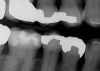

(37.) Fractured cusp after adhesive bonding and polishing of the finish line, resulting in a smooth and seamless transition and 25-month follow up radiograph where the adhesively bonded fracture line is visible.

Figure 37

(38.) Fractured cusp after adhesive bonding and polishing of the finish line, resulting in a smooth and seamless transition and 25-month follow up radiograph where the adhesively bonded fracture line is visible.

Figure 38

(39.) Fractured cusp after adhesive bonding and polishing of the finish line, resulting in a smooth and seamless transition and 25-month follow up radiograph where the adhesively bonded fracture line is visible.

Figure 39

(40.) Fractured cusp after adhesive bonding and polishing of the finish line, resulting in a smooth and seamless transition and 25-month follow up radiograph where the adhesively bonded fracture line is visible.

Figure 40